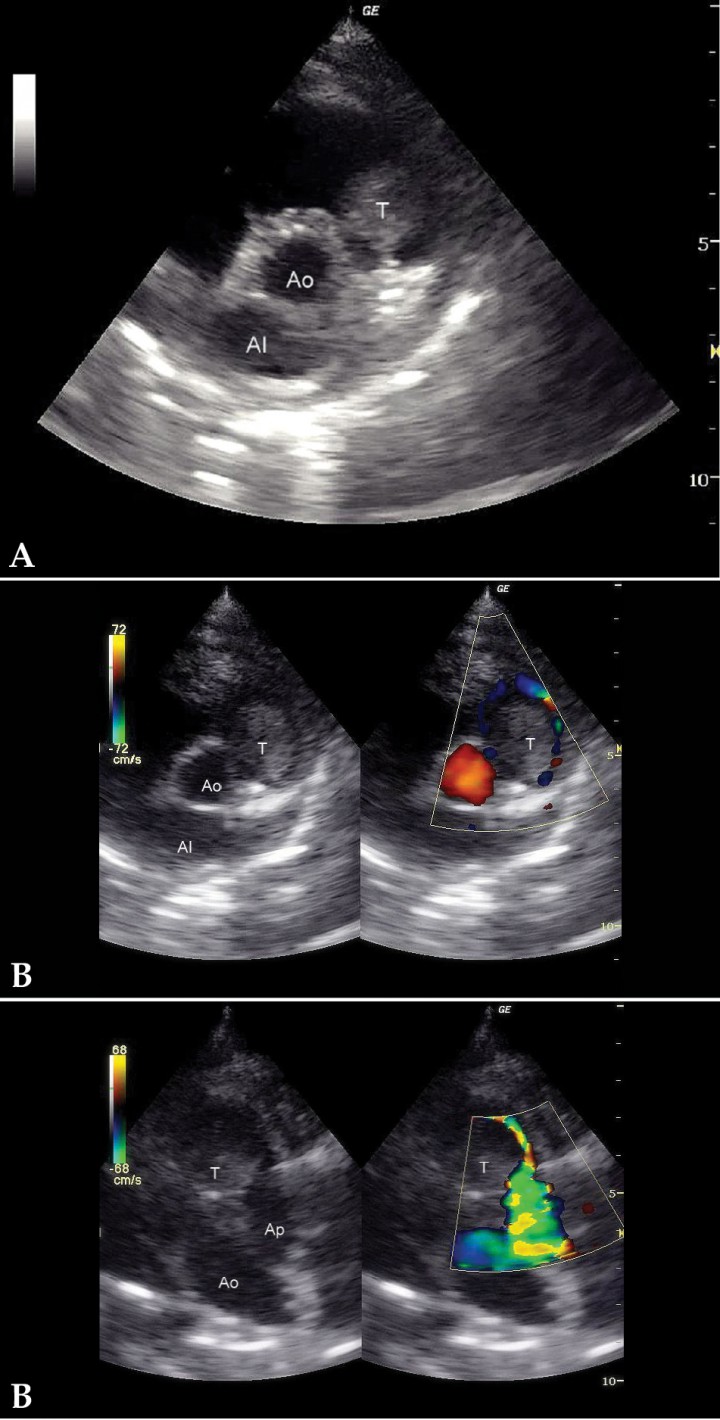

(A) Corte paraesternal derecho, eje largo, 4 cámaras. Severa dilatación del atrio derecho. (B) Corte paraesternal derecho, eje corto. Presencia de una masa intraluminal en tracto de salida derecho. (C) Corte craneal izquierdo. Presencia de una masa intraluminal en tracto de salida derecho. AD: atrio derecho; AI: atrio izquierdo; VD: ventrículo derecho; VI: ventrículo izquierdo; T: tumor; Ao: aorta; AI: atrio izquierdo; Ap: arteria pulmonar.

- Presencia de una masa intraluminal de dos por tres centímetros en tracto de salida derecho (Figs. 3B y 3C), que produce una obstrucción al flujo de salida y, por tanto, una reducción del caudal a través de la arteria pulmonar. El flujo laminar de salida a 1,4 m/s se vuelve turbulento a su paso por la masa, a la que rodea claramente (Fig. 4), provocando una aceleración del flujo hasta los 2,9 m/s (Fig. 5).

Figura 4

(A) Corte paraesternal derecho, eje corto. (B) Corte craneal izquierdo. Doppler color con flujo sanguíneo rodeando la masa demostrando obstrucción mecánica del flujo. T: tumor; Ao: aorta; Ap: arteria pulmonar.